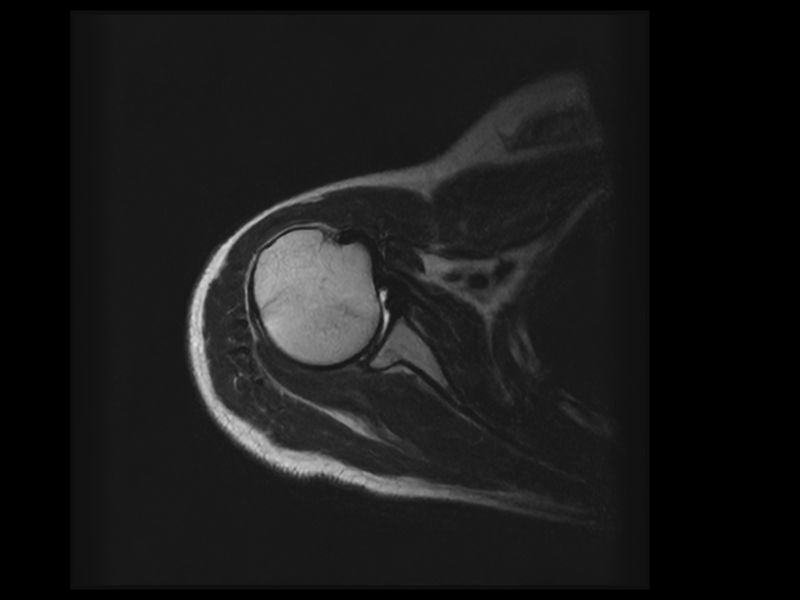

Esaote introduces Artificial Intelligence into its MRI systems as a fully integrated and customized solution. The new technological platform, e‑SPADES, consisting of advanced HW and sophisticated SW algorithms such as HyperClarity delivers unparalleled image quality.

HyperClarity

Step into a new era for Esaote systems with HyperClarity, powered by SwiftMR™, a trademark of AIRS Medical Inc. This advanced integrated feature significantly enhances image quality by improving resolution, reducing noise, and providing physicians with a powerful tool for more consistent clinical outcomes.

Clinical Images